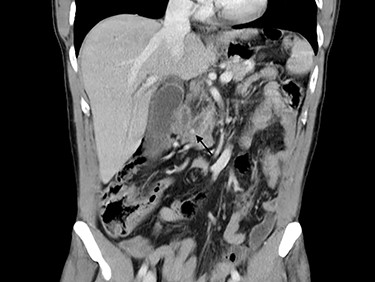

A trans-cystic cholangiography was then performed, using a 5.0 Fr COOK® Medical ureteral catheter inserted through epigastrium. The augmented caliber of CBD and the presence of prepapillary lithiasis were confirmed. No contrast could pass into the duodenum (Fig. 3).

Trans-cystic cholangiography demonstrating prepapillary lithiasis.